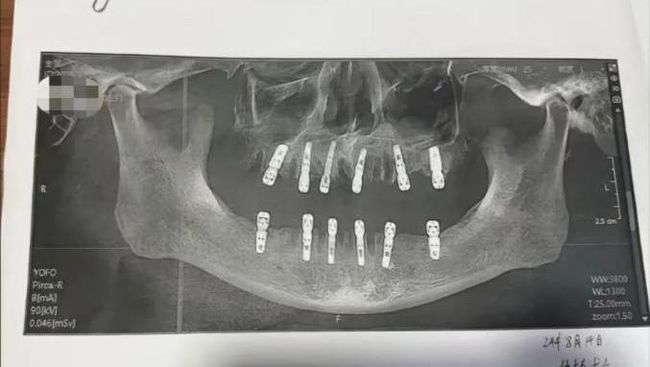

Foto: Seorang pria lanjut usia meninggal dunia setelah mencabut menjalani pencabutan gigi. (tangkapan layar viral OddityCentral)

Anak Huang, Shu, melaporkan kasus ini setelah menemukan bukti ayahnya telah menandatangani persetujuan untuk pencabutan 23 gigi dan pemasangan 12 gigi baru. Prosedur yang dilakukan termasuk pembuatan lubang di tengkorak dan rahang bawah, yang dikenal dengan istilah 'immediate restoration' atau 'restorasi segera.'